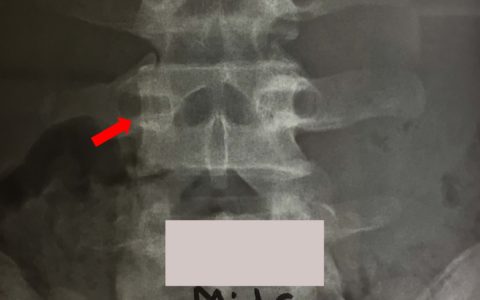

Στην Αυχενική Μοίρα της Σπονδυλικής Στήλης υπάρχει εξαιρετικά πλούσιο και πολύπλοκο δίκτυο αγγείων (αρτηριών και φλεβών). Οι χειρουργικές επεμβάσεις οι οποίες πραγματοποιούνται προσθίως και οπισθίως στην περιοχή αυτή, ενέχουν τον κίνδυνο τραυματισμού των αγγείων, με συνέπεια την πρόκληση σημαντικών επιπλοκών. Στην ομιλία που ακολουθεί αναλύονται: Η πορεία των αγγείων Το είδος των χειρουργικών επεμβάσεων οι